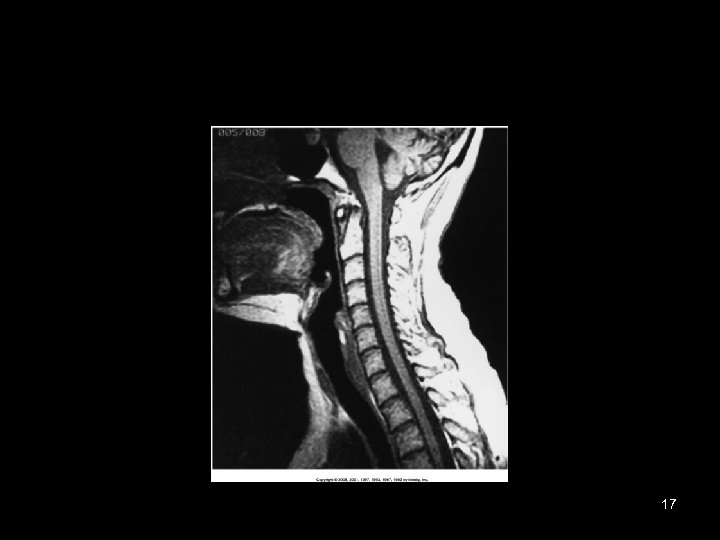

17